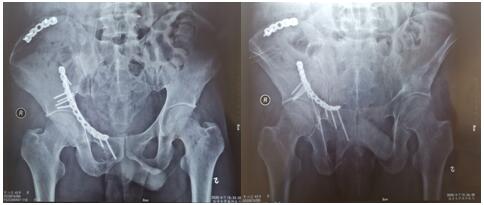

術后影像學資料如下:

骨盆骨折多由高能量損傷所致,多伴有合并癥或多發傷,處理棘手,致殘率高達50%~60%。經過孟澤祖主治醫師、李鵬鵬住院醫師的精心管理與辛勤付出,患者曹某腰椎骨折術后病情恢復良好。于2020年4月1日在全麻下行骨盆粉碎性骨折切開復位內固定術,患者多處骨盆粉碎性骨折,病情復雜,手術時間長,術中出血多。首次采用改良stoppa+右髂后上棘聯合入路,手術順利,術后病情不穩定,經過主管醫師孟澤祖與全科骨干醫師、護士的通力合作與堅守,術后病情日趨穩定。復查下肢血管超聲提示:未見明顯血栓。患者曹某在我院經過標準化、專業化的綜合治療后,患者病情恢復良好,神經損傷癥狀已基本恢復,傷口I級愈合,患者帶著滿意的笑容康復出院了。